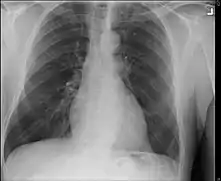

- Lungs: abnormal chest X-ray with:

- nodules,

- infiltrates or

- cavities